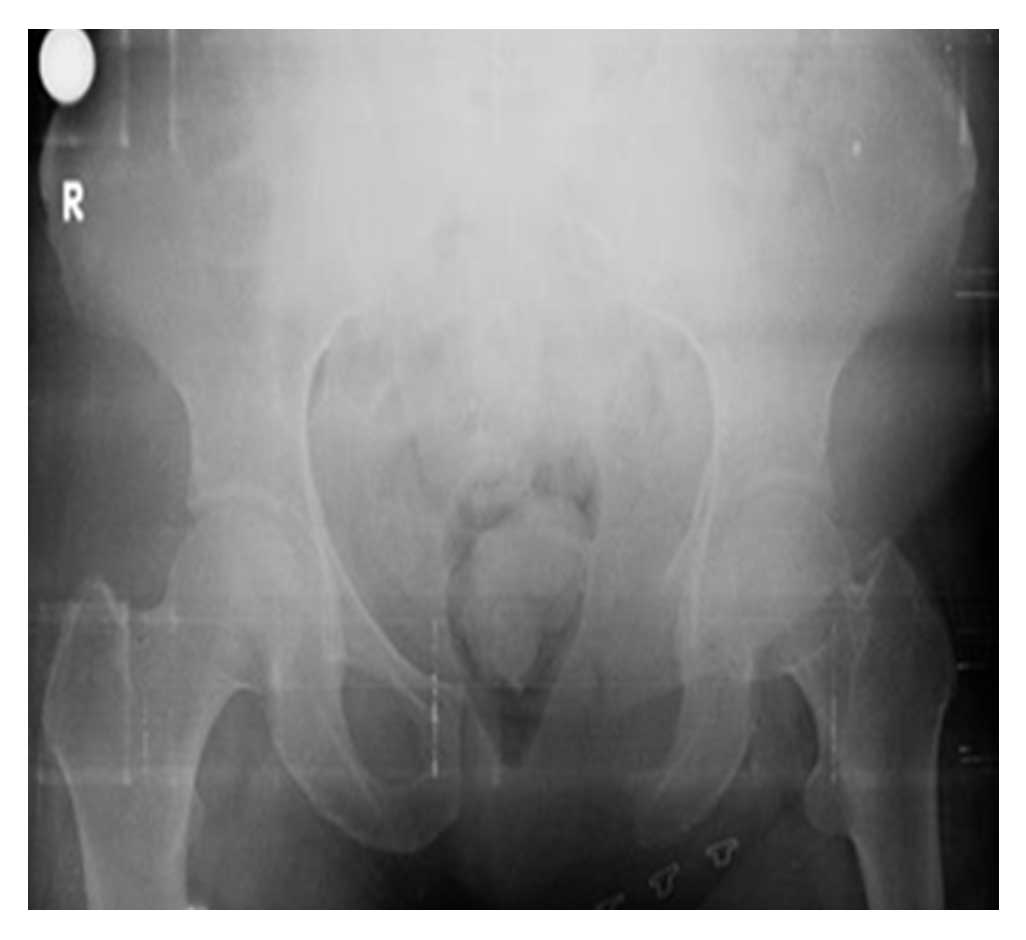

Ameliyat Sonrası: Röntgende sol Tip-III rezeksiyon uygulanımı görülmekte.